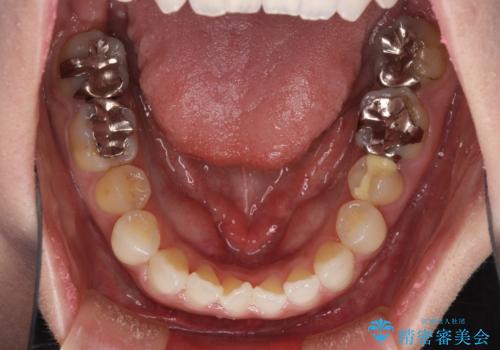

前歯のデコボコをすっきりと インビザライン矯正

- 前歯のデコボコを治したいとのことで来院された患者様です。

下顎が前方位にある方であったため、下顎の歯列全体の後方移動とIPR(歯と歯の間を削る)によってデコボコが解消するように設計し、インビザラインにより治療を行うこととしました。